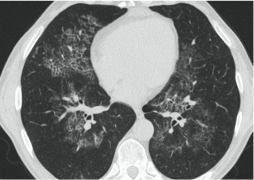

- Изменения в легких при КТ (рентгенографии), типичные для вирусного поражения (объем поражения значительный или субтотальный; КТ 3 - 4)

- ОРДС

- ОДН с необходимостью респираторной поддержки (инвазивная вентиляции легких)

- Изменения в легких при КТ (рентгенографии), типичные для вирусного поражения критической степени (объем поражения значительный или субтотальный; КТ 4) или картина ОРДС.

КТ имеет высокую чувствительность в выявлении изменений в легких, характерных для COVID-19. Применение КТ целесообразно для первичной оценки состояния ОГК у пациентов с тяжелыми прогрессирующими формами заболевания, а также для дифференциальной диагностики выявленных изменений и оценки динамики процесса. КТ позволяет выявить характерные изменения в легких у пациентов с COVID-19 еще до появления положительных лабораторных тестов на инфекцию с помощью МАНК. В то же время, КТ выявляет изменения легких у значительного числа пациентов с бессимптомной и легкой формами заболевания, которым не требуется госпитализация. Результаты КТ в этих случаях не влияют на тактику лечения и прогноз заболевания при наличии лабораторного подтверждения COVID-19. Поэтому массовое применение КТ для скрининга асимптомных и легких форм болезни не рекомендуется.